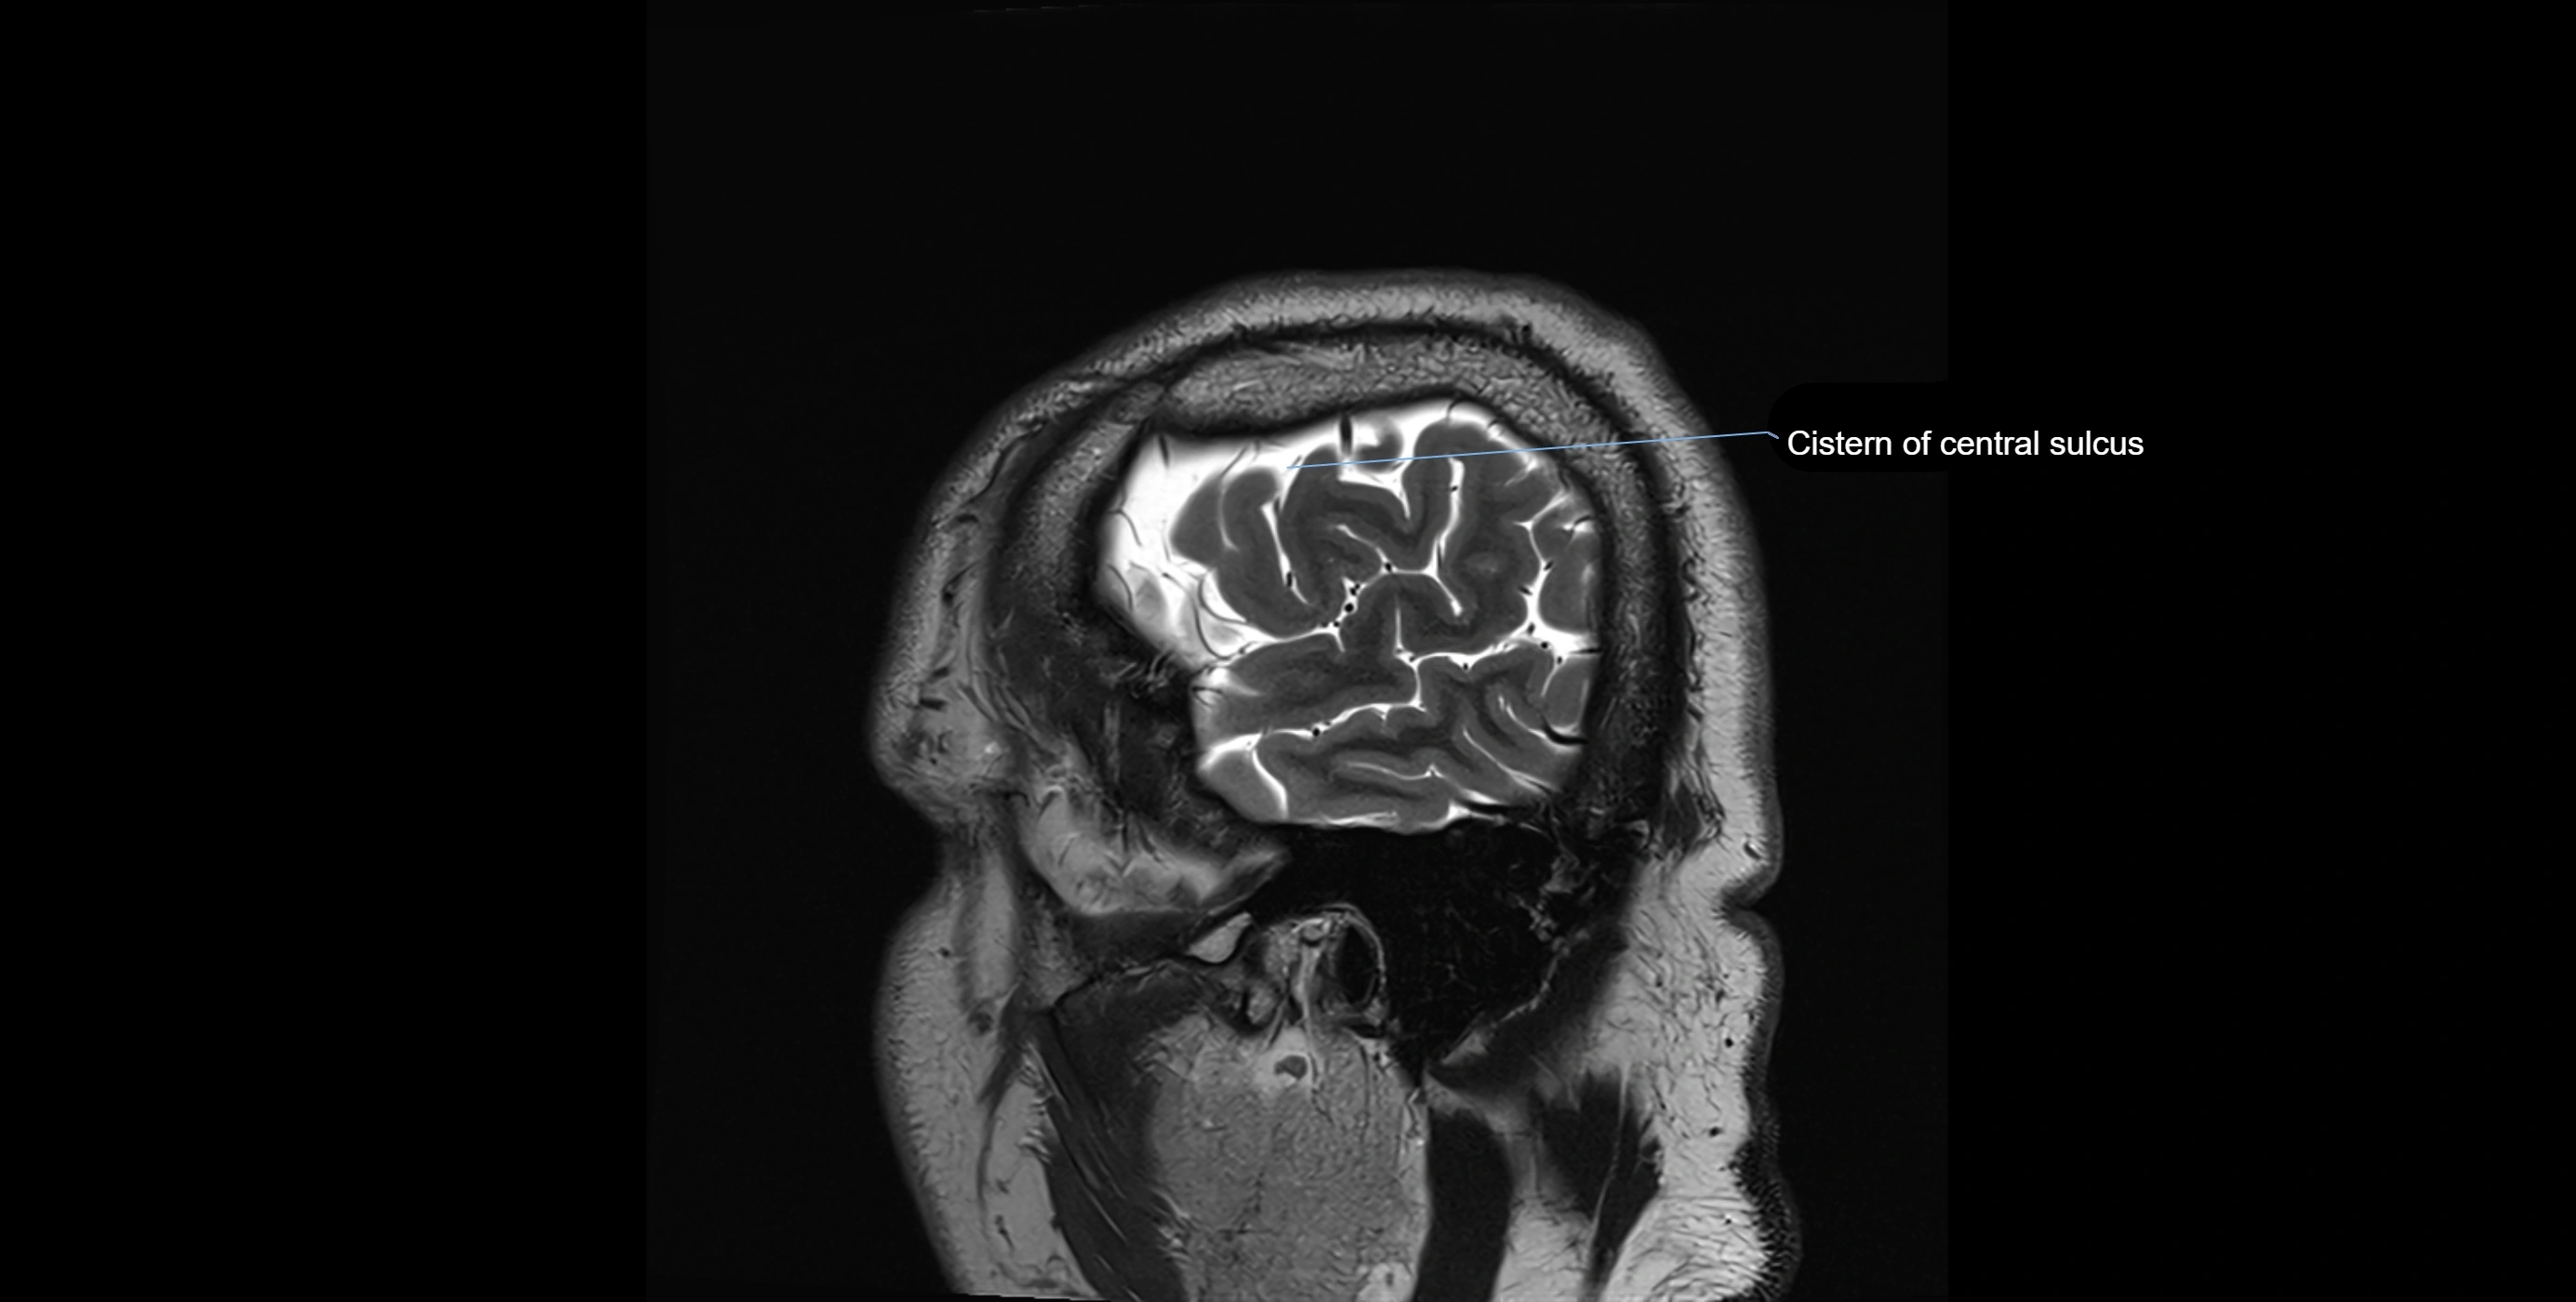

CT image

image